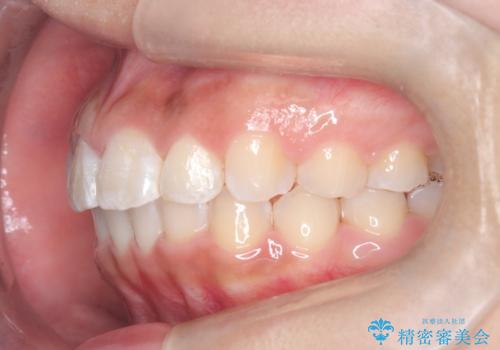

マウスピース矯正で前歯のガタツキを改善! ワイヤー矯正併用でかみ合わせもしっかり治します

- 前歯のガタツキが気になると来院されました。

マウスピース矯正治療を選択しました。

この症例では、奥歯のかみ合わせの改善を目的にワイヤー矯正を併用しました。奥歯のかみ合わせをより緊密にするため、また短期間に治療するためにはワイヤー矯正が適していることがあります。